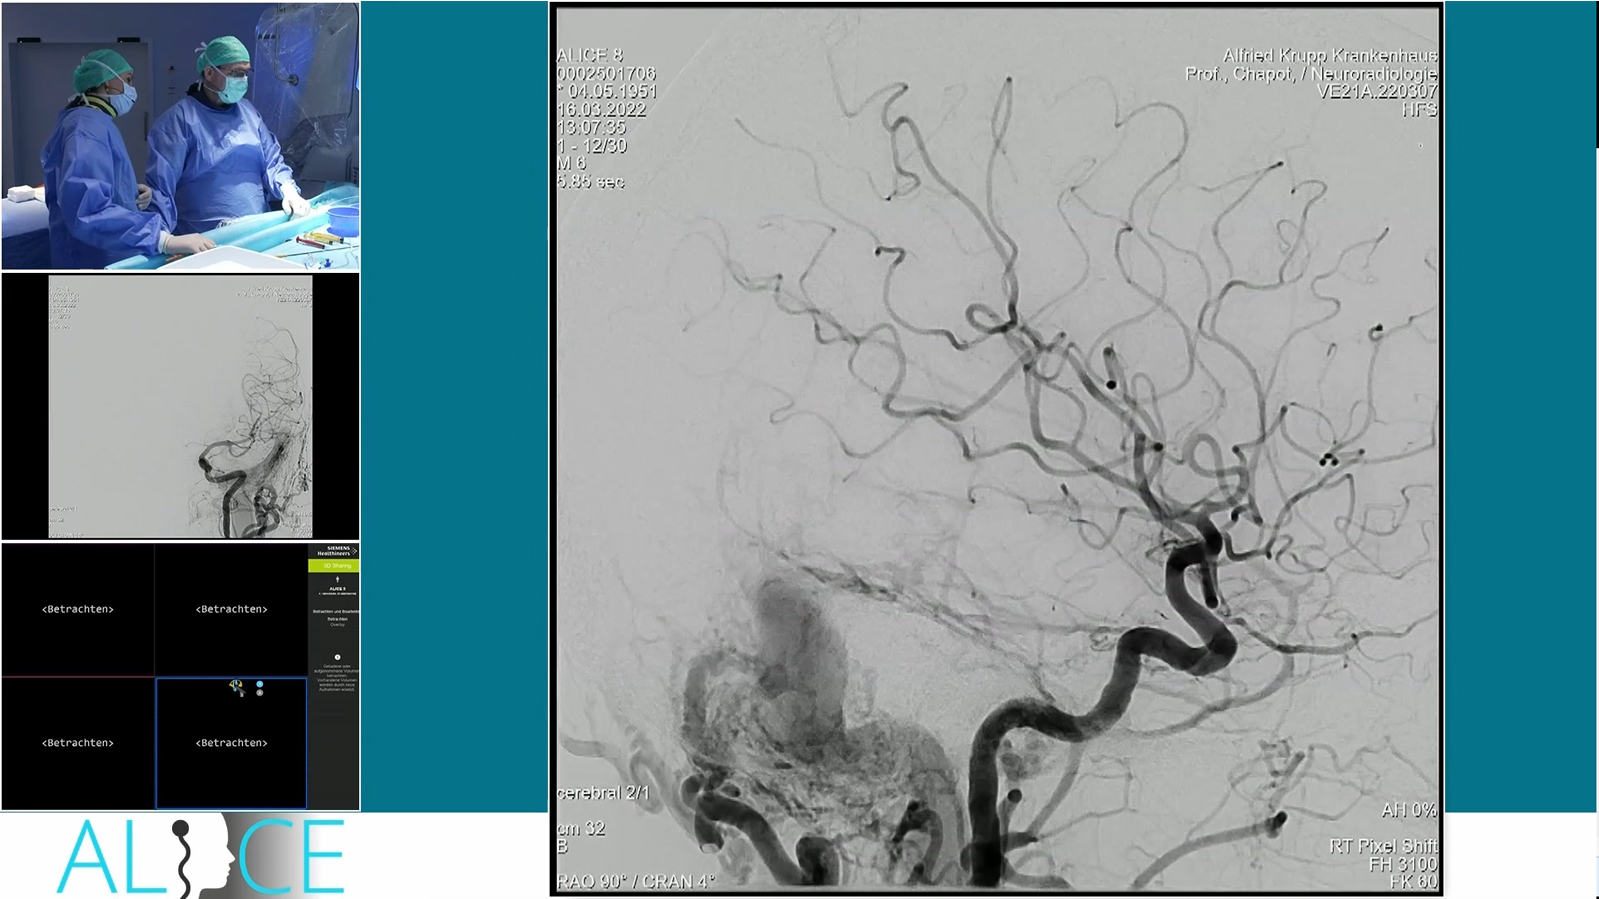

Ruptured hypothalamic AVM treated by transarterial embolization with PHIL

Watch the video